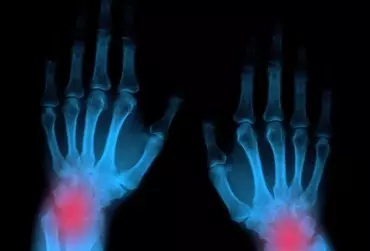

Reumatoidalne zapalenie stawów to przewlekła, zapalna, immunologicznie zależna choroba układowa tkanki łącznej. Charakteryzuje się nieswoistym, symetrycznym zapaleniem stawów, obecnością zmian pozastawowych oraz występowaniem licznych powikłań układowych prowadzących do niepełnosprawności, a w stadium zaawansowanym – do trwałego kalectwa.